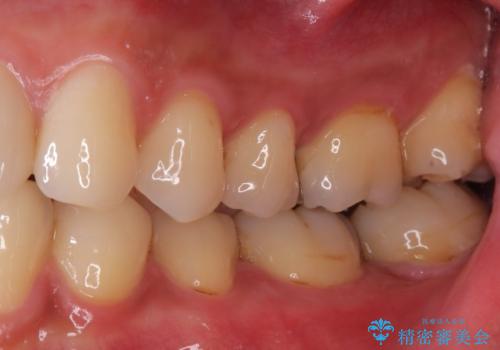

セラミックインレーで治療を行いました。

神経の近くまで虫歯が広がっていたため、虫歯の除去後、神経を保護する材料をおきセラミックインレーで治療を行いました。

保険適応の銀歯ではどうしても歯との適合が悪く隙間が出来てしまったり、材質の劣化により再び虫歯になってしまうケースがとても多いです。